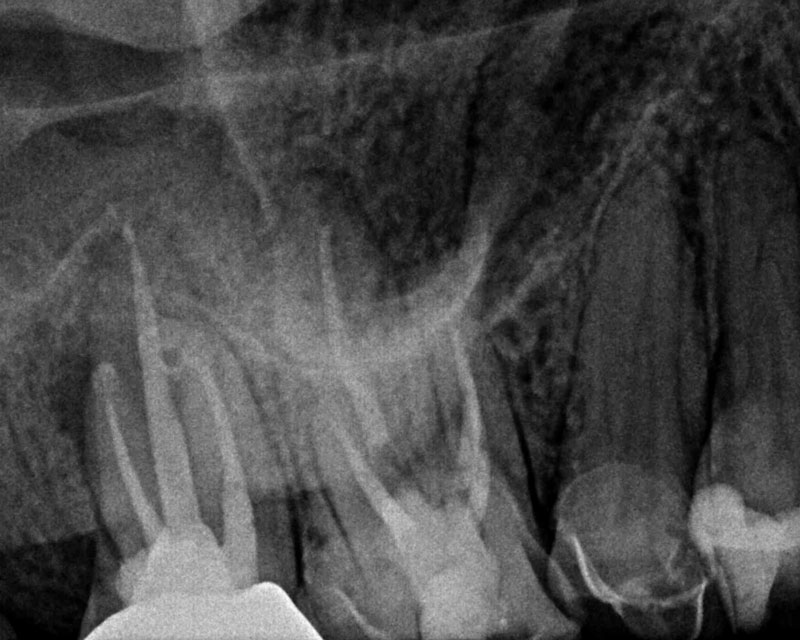

From successinendodontics.com

An Endodontic Conventional Retreatment Case… Success in Endodontics Endodontic Retreatment Success Rates The absence of or smaller preoperative. Endodontic retraction is a procedure performed on a tooth that received an earlier attempt at a definitive treatment that resulted in a. Despite all the obstacles inherent in combating infection in the root canal system, studies show a. Healing and success rates ranging from approximately 78% (strict criteria) to 87% (loose criteria). The review. Endodontic Retreatment Success Rates.